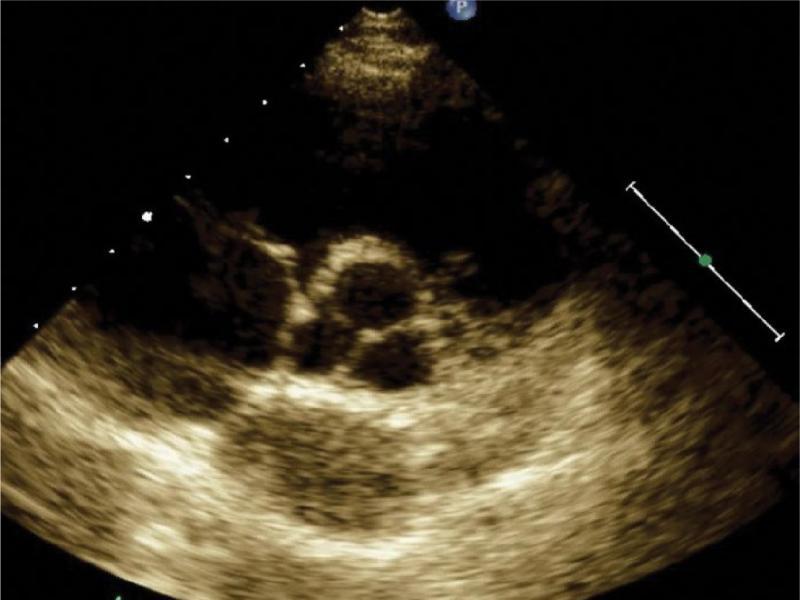

Color Doppler is the basic modality for the assessment of regurgitation. The method detects a regurgitant jet and allows for identifying the site of leakage as well as for preliminary qualitative assessment of the magnitude of regurgitation (width and extent of the jet); regurgitation jet area may be planimetrically assessed, the ratio of its area to the area of the heart cavity to which it returns may be evaluated, as well as regurgitation depth may be measured. The proximal isovelocity surface area (PISA) measurement (flow convergence) is recommended for the quantitative assessment of regurgitation. By changing the color scale (Nyquist limit), the flow convergence proximal to the stenotic orifice (PISA) may be visualized and the orifice area may be measured. A two-dimensional color Doppler image of regurgitation, together with the spectrum of valvular regurgitation recorded by continuous wave Doppler allows for the assessment of the severity of regurgitation. Conventionally measured and calculated regurgitant parameters include vena contracta width (VCW), PISA radius, effective regurgitant orifice (ERO), and regurgitant volume. Three-dimensional echocardiography, which allows for a more precise visualization of cusps and annuli (Fig. 1), offers additional possibilities of valvular assessment. If the diagnosis cannot be reached using transthoracic echocardiography, transesophageal echo should be performed in the case of suspected valvular disease.

A three-dimensional view of mitral and tricuspid valves. Leaflet morphology is visualized. The three-dimensional view allows for the assessment of the tricuspid valve in a transverse plane. TV – tricuspid valve, MV – mitral valve